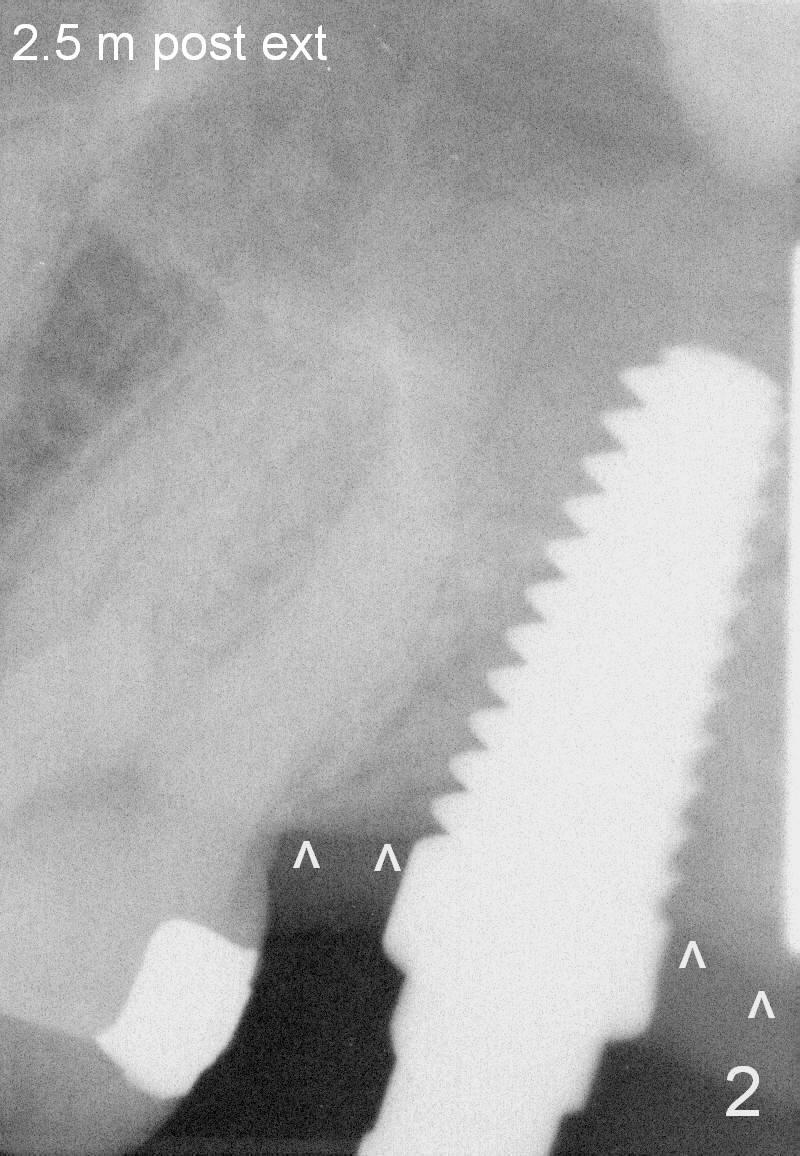

The tooth #15 is going to be extracted due to repeated furcal infection; the distal crest appears to be flat (Fig.1 ^). Two and a half months post extraction, a 6x17 mm tap is placed (Fig.2) prior to placement of a 8x14 mm tissue-level implant (Fig.3). It is apparent that the crest bone has started bone loss (^).